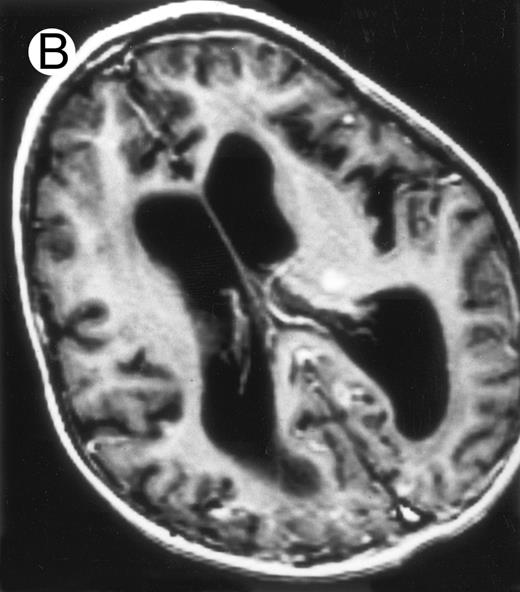

Three different aspects of brain imaging in HLH patients. (A) CT scan of a 3-month-old baby showing a large subdural effusion, several necrotic areas and hypodensities of the white matter. (B) Brain magnetic resonance of a 14-month-old boy showing large confluent areas of hypersignal in T2-weighted images. (C) Large symmetrical necrotic areas of cerebellar white matter in a 41/2-year-old girl (MRI).

Nine patients were transplanted soon after the remission of initial CNS and systemic manifestations. All of these patients had meningitis only as the CNS manifestation. The median delay between diagnosis and BMT was 4 months (range, 2 to 14 months). Two patients died of BMT-related toxicity (both recipients of an HLA-identical BMT). Seven patients are alive and well with normal neurological examination, normal CSF tap, and normal cognitive development after a follow-up of 18 to 132 months (median, 55 months) (four recipients of an identical BMT and three of a partially-identical BMT). After BMT, chimerism studies demonstrated full or partial engraftment in all of these seven patients. MRI was performed before and after the transplantation in three cases. Two patients had a normal MRI or an isolated subarachnoidal and subdural space dilatation before transplantation and a normal MRI, respectively 4 years and 18 months after transplantation. One patient had white matter abnormalities before transplantation, which remained identical 2 years after transplantation (Fig 4).

MRI of a symptom-free 31/2-year-old child who received BMT at 18 months showing the persistent white matter abnormalities.